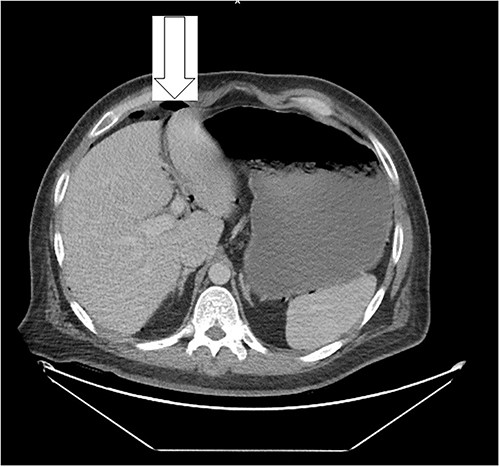

Dietary consultation started him on a gastroparesis diet where he progressed well. Upon hospital discharge CT showed a moderate volume of pneumoperitoneum with a small volume of perihepatic and perisplenic ascites. No areas of focal bowel wall thickening were noted (see Fig. 4).

Similar appearance of moderate volume pneumoperitoneum compared with last CT.